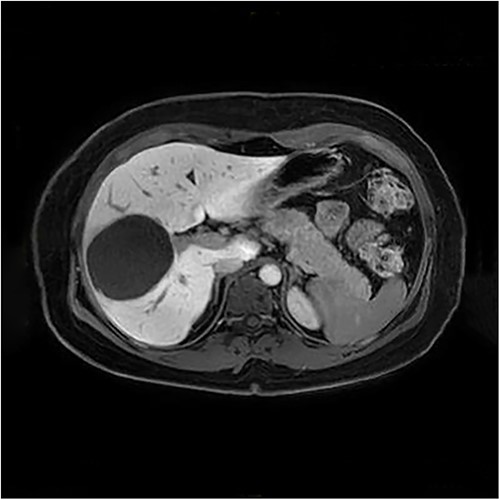

The presenting patient was a 40-year-old Brazilian native who had lived in Europe for ~26 years. Initially, the patient presented to her general practitioner with upper right quadrant pain. An ultrasound study (Fig. 1) showed a small hyperechoic lesion in segment VII measuring ~0.8 × 0.9 cm. Follow-up studies showed an expanding lesion with newer hyperechoic portions. In 2020 a liver specific magnetic resonance imaging (MRI) (Fig. 2) was performed. Here, again, the cyst was expanding, septated and had reached a size of 7.3 × 6 × 6.5 cm. A Echinococcus infection was considered, however, repetitive EIisa for Echinococcus sp./IgG was negative. The alpha protein was 2 ug/L, and well within normal limits. Due to increasing discomfort, an upper gastrointestinal tract endoscopy was performed. Here, gastritis and gastro-intestinal neoplasia could be excluded.

Unfortunately, histopathological examination showed only chronic inflammation with fibrosis. No evidence of malignant transformation was noted. Even in the postoperatively performed follow-up MRI, no malignant criteria could be identified. However, as a result of the extreme discomfort felt by the patient as well as the still unclear nature of the lesion, the decision was made to perform a partial en bloc liver resection of segments V, VI and VII.

The histopathological work-up revealed the already described macroscopic cystic lesion (Fig. 4). More precisely, a pseudocyst, which differs from a cyst in that it does not possess an epithelial lining. Within the pseudocyst, necrotic liver parenchyma was found. In addition, and more surprisingly, parasites (Fig. 5) were found within the portal fields, partially within the blood vessels. These appeared to be schistosomas. It appeared that the necrosis within the pseudocyst was formed pursuant to ischemia. Finally, proof of schistosomiasis mansoni eggs in stool cultures was able to definitively render the diagnosis. An antihelmintic therapy with praziquantel was begun, under which the patient was able to completely recover.